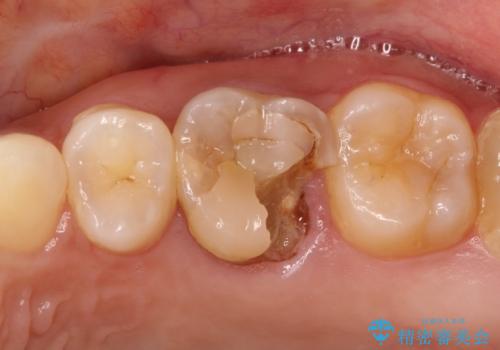

奥歯のむし歯を治したい セラミッククラウンによる補綴治療

大きい虫歯 根管治療〜オールセラミッククラウン